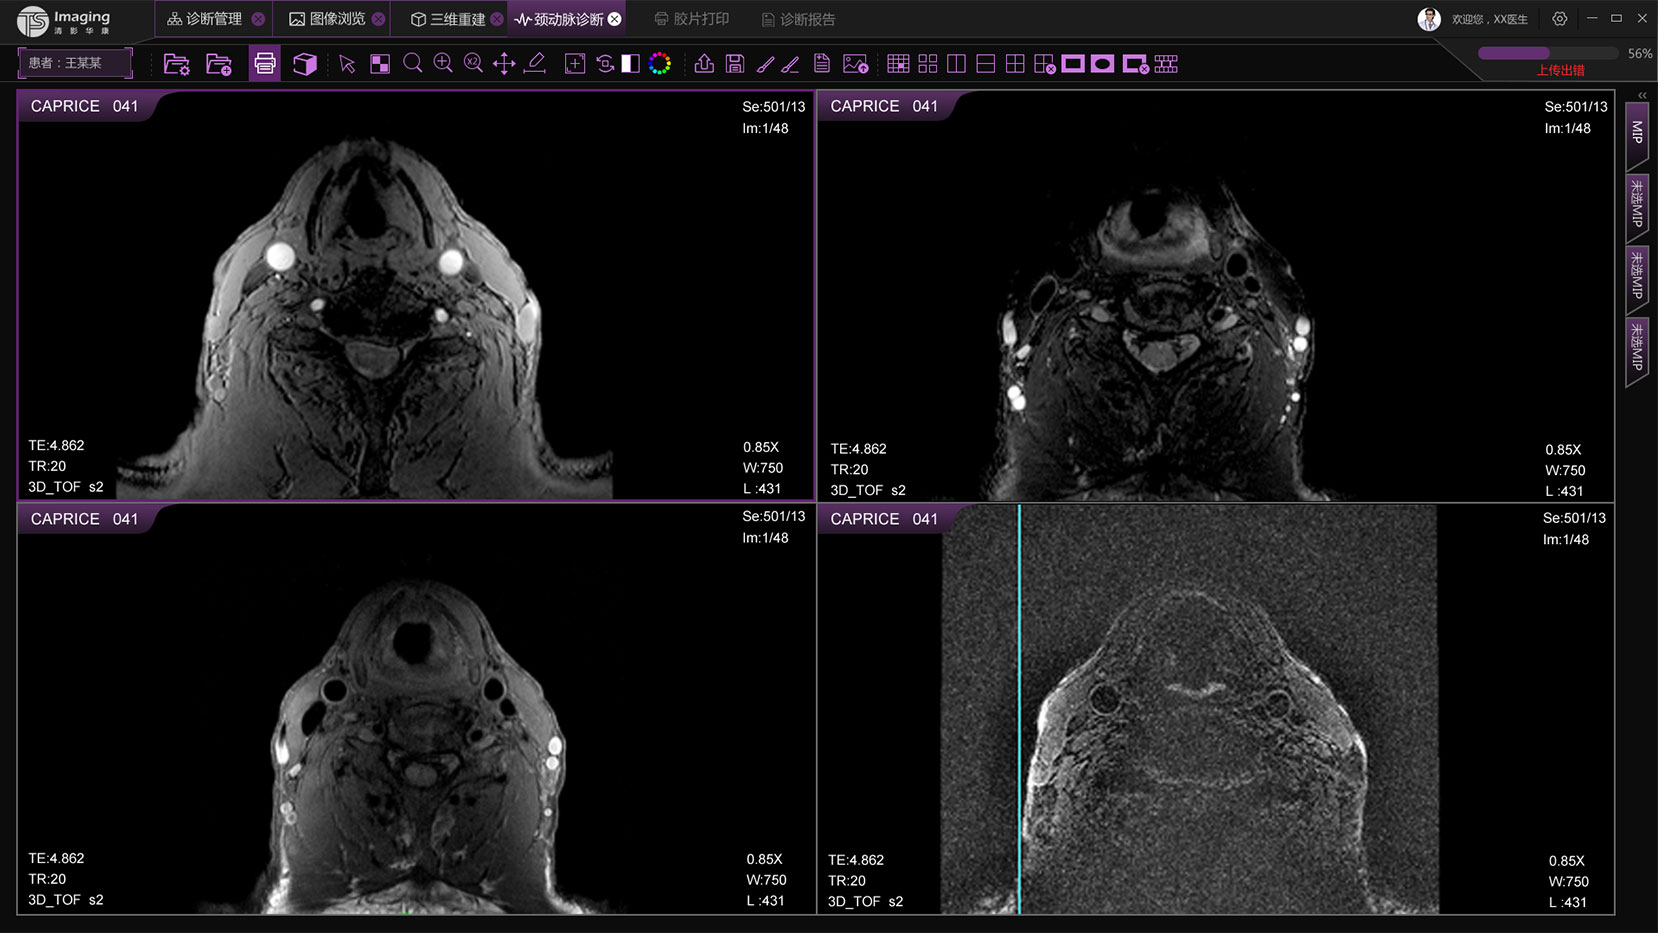

頸動(dòng)脈診斷頁(yè)面

頸動(dòng)脈診斷頁(yè)面整體布局和三維重建比較相似,最大的區(qū)別是右側(cè)的操作區(qū)域,血管分析都為按鍵操作,通過(guò)間隔的大小分成三部分。單層切片除了按鍵還有下拉菜單的操作。

頸動(dòng)脈診斷原型